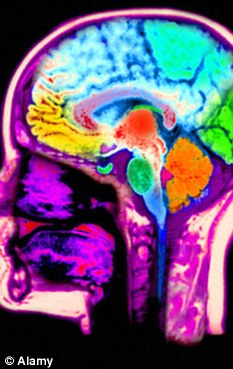

研究人员对志愿者实施相同刺激,每次刺激后用1至20分衡量她们的疼痛感,同时借助功能性磁共振成像技术(MRI)监测志愿者大脑活动。研究人员让志愿者注视不同照片,照片内容从伴侣、陌生人到蜘蛛、蛇等各不相同。结果显示,当志愿者看到伴侣照片时,代表身体感受到疼痛程度的分数显著降低。研究人员发现,志愿者注视伴侣照片时,大脑前额叶皮层活跃。与伴侣恋爱或结婚时间越长,受伴侣支持越多,这一区域活跃程度越高。

先前有研究显示,前额叶皮层与安全感相关,能够抑制大脑对害怕和焦虑的反应。加州大学洛杉矶分校研究人员在美国《国家科学院学报》(PNAS)发表论文说,这一区域也能缓解疼痛。研究人员还发现,当志愿者注视“另一半”照片时,负责压力反应的大脑背侧前扣带皮层欠活跃。

Brain: The ventromedial prefrontal cortex was linked to feelings of safety

Although it has long been hypothesized that attachment figures provide individuals with a sense of safety and security, the neural mechanisms underlying attachment-induced safety have not been explored. Here, we investigated whether an attachment figure acts as a safety signal by exploring whether viewing an attachment figure during a threatening experience (physical pain) led to increased activity in a neural region associated with safety signaling, the ventromedial prefrontal cortex (VMPFC), and corresponding reductions in pain. Female participants in long-term romantic relationships were scanned as they received painful stimuli while viewing pictures of their partner and control images (stranger, object). Consistent with the idea that the attachment figure may signal safety, results revealed that viewing partner pictures while receiving painful stimulation led to reductions in self-reported pain ratings, reductions in pain-related neural activity (dorsal anterior cingulate cortex, anterior insula), and increased activity in the VMPFC. Moreover, greater VMPFC activity in response to partner pictures was associated with longer relationship lengths and greater perceived partner support, further highlighting a role for the VMPFC in responding to the safety value of the partner. Last, greater VMPFC activity while viewing partner pictures was associated with reduced pain ratings and reduced pain-related neural activity. An implication of these findings is that, in the same way that stimuli that historically have threatened survival (e.g., snakes, spiders) are considered to be prepared fear stimuli, attachment figures, who have historically benefited survival, may serve as prepared safety stimuli, reducing threat- or distress-related responding in their presence.

The researchers discovered activity in the ventromedial prefrontal cortex which is associated with a feeling of safety.

The longer the women had been in the relationship and the more supported they were by their partner, the greater the level of activity in the ventromedial prefrontal cortex, or VMPFC.

The VMPFC is capable of inhibiting other pathways in the brain responsible for fear and anxiety. This area was also able to reduce pain, the researchers found.

Researchers also discovered that the dorsal anterior cingulate cortex, an area responsible for stress response, was less active when the women were looking at the photos of their other halves.